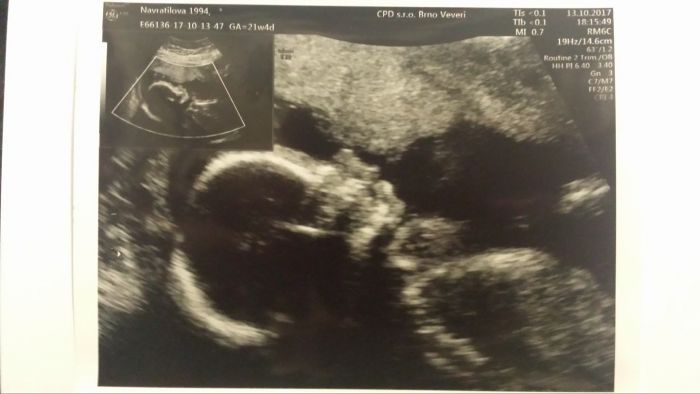

Ahoj, tak nám kontrola dopadla taky dobře, máme potvrzenou holčičku a je zdravoučká

míry prý kolem 25 cm a 400g.

[1030643] 21.týden